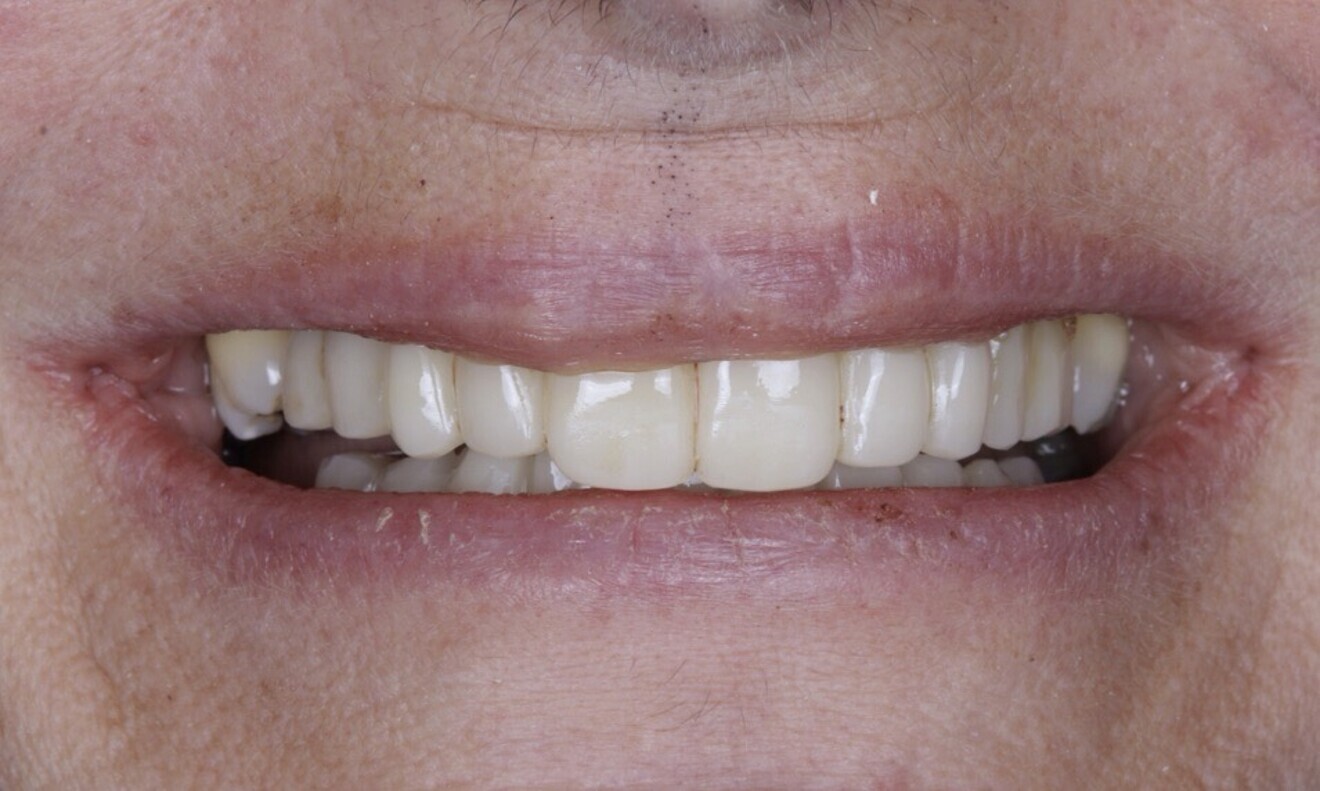

The soft tissue was in good condition, and the definitive restorations were placed (Figs. 76 & 77). After placing the definitive restorations, oral hygiene instructions were given to ensure proper care and prevent complications. Additionally, the occlusion was carefully checked and adjusted as needed (Figs. 78–83).

Figs. 78–82: The definitive restorations were placed, and occlusal adjustments were performed.